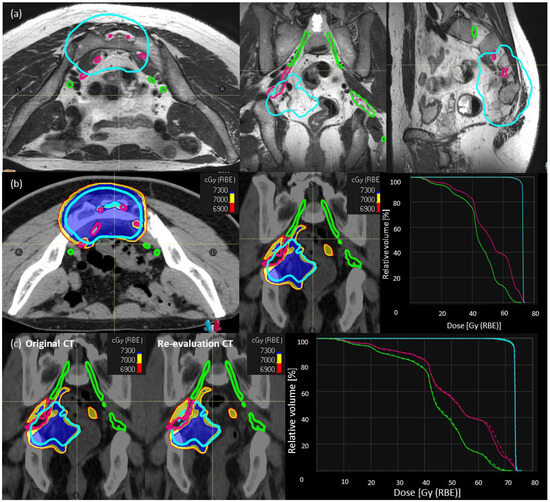

2.2. Treatment Simulation and Planning: Clinical

2.3. SNSo-CIRT Strategy

SNSo-CIRT Composed of Three Step Approach